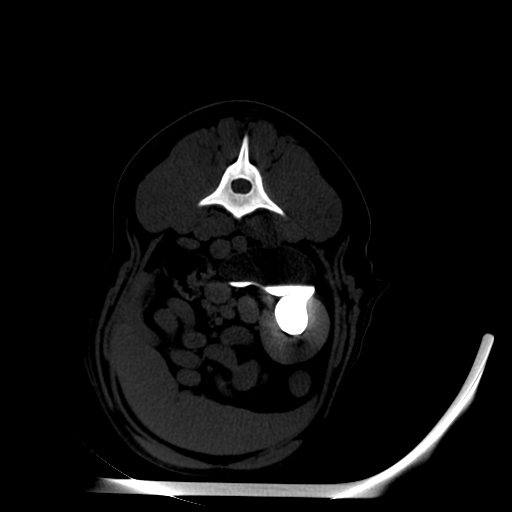

The modern Through-Silicon-Via (TSV) stacked CT detectors provide high-resolution images with low noise and high contrast, while the 40 cm gantry and 30 cm field-of-view provide additional space and information for your diagnostic needs versus VetTom 8.